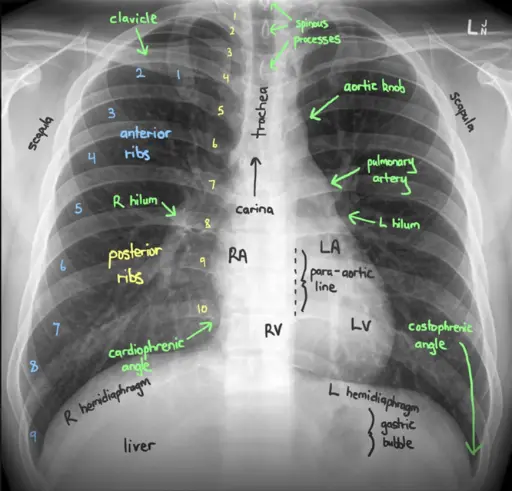

A – AIRWAY: Đường hô hấp (đánh giá cây khí quản phế quản)

- Khí quản có nằm giữa không? Có bất kỳ khuyết tật hay hẹp nào không?

- Tìm góc carina và điểm phân nhánh của các phế quản chính phải và trái.

B – BREATHING: Hô hấp (phổi và màng phổi)

- Đánh giá các trường phổi, các vết nứt, góc sườn hoành.

- Có dấu hiệu xẹp phổi, tràn dịch màng phổi, đặc phổi, khối u, phù phổi không?

- Khảo sát góc sườn hoành và dấu hiệu bóng bờ (silhouettes)

C – CIRCULATION: Tuần hoàn (tim, cung động mạch chủ, mạch máu phổi)

- Ranh giới tim có rõ ràng không?

- Vị trí và kích thước tim, giãn trung thất, vấn đề về cung động mạch chủ, màng ngoài tim, đầy đặn các hạch bạch huyết, sự thay đổi của mạch máu phổi?

D – DISABILITY: Tàn tật (bệnh lý xương từ ngoài vào trong)

- Khám tất cả các cấu trúc xương từ xương cánh tay, đốt sống đến các xương sườn phía trước và phía sau – có gãy xương hay bất thường nào không?